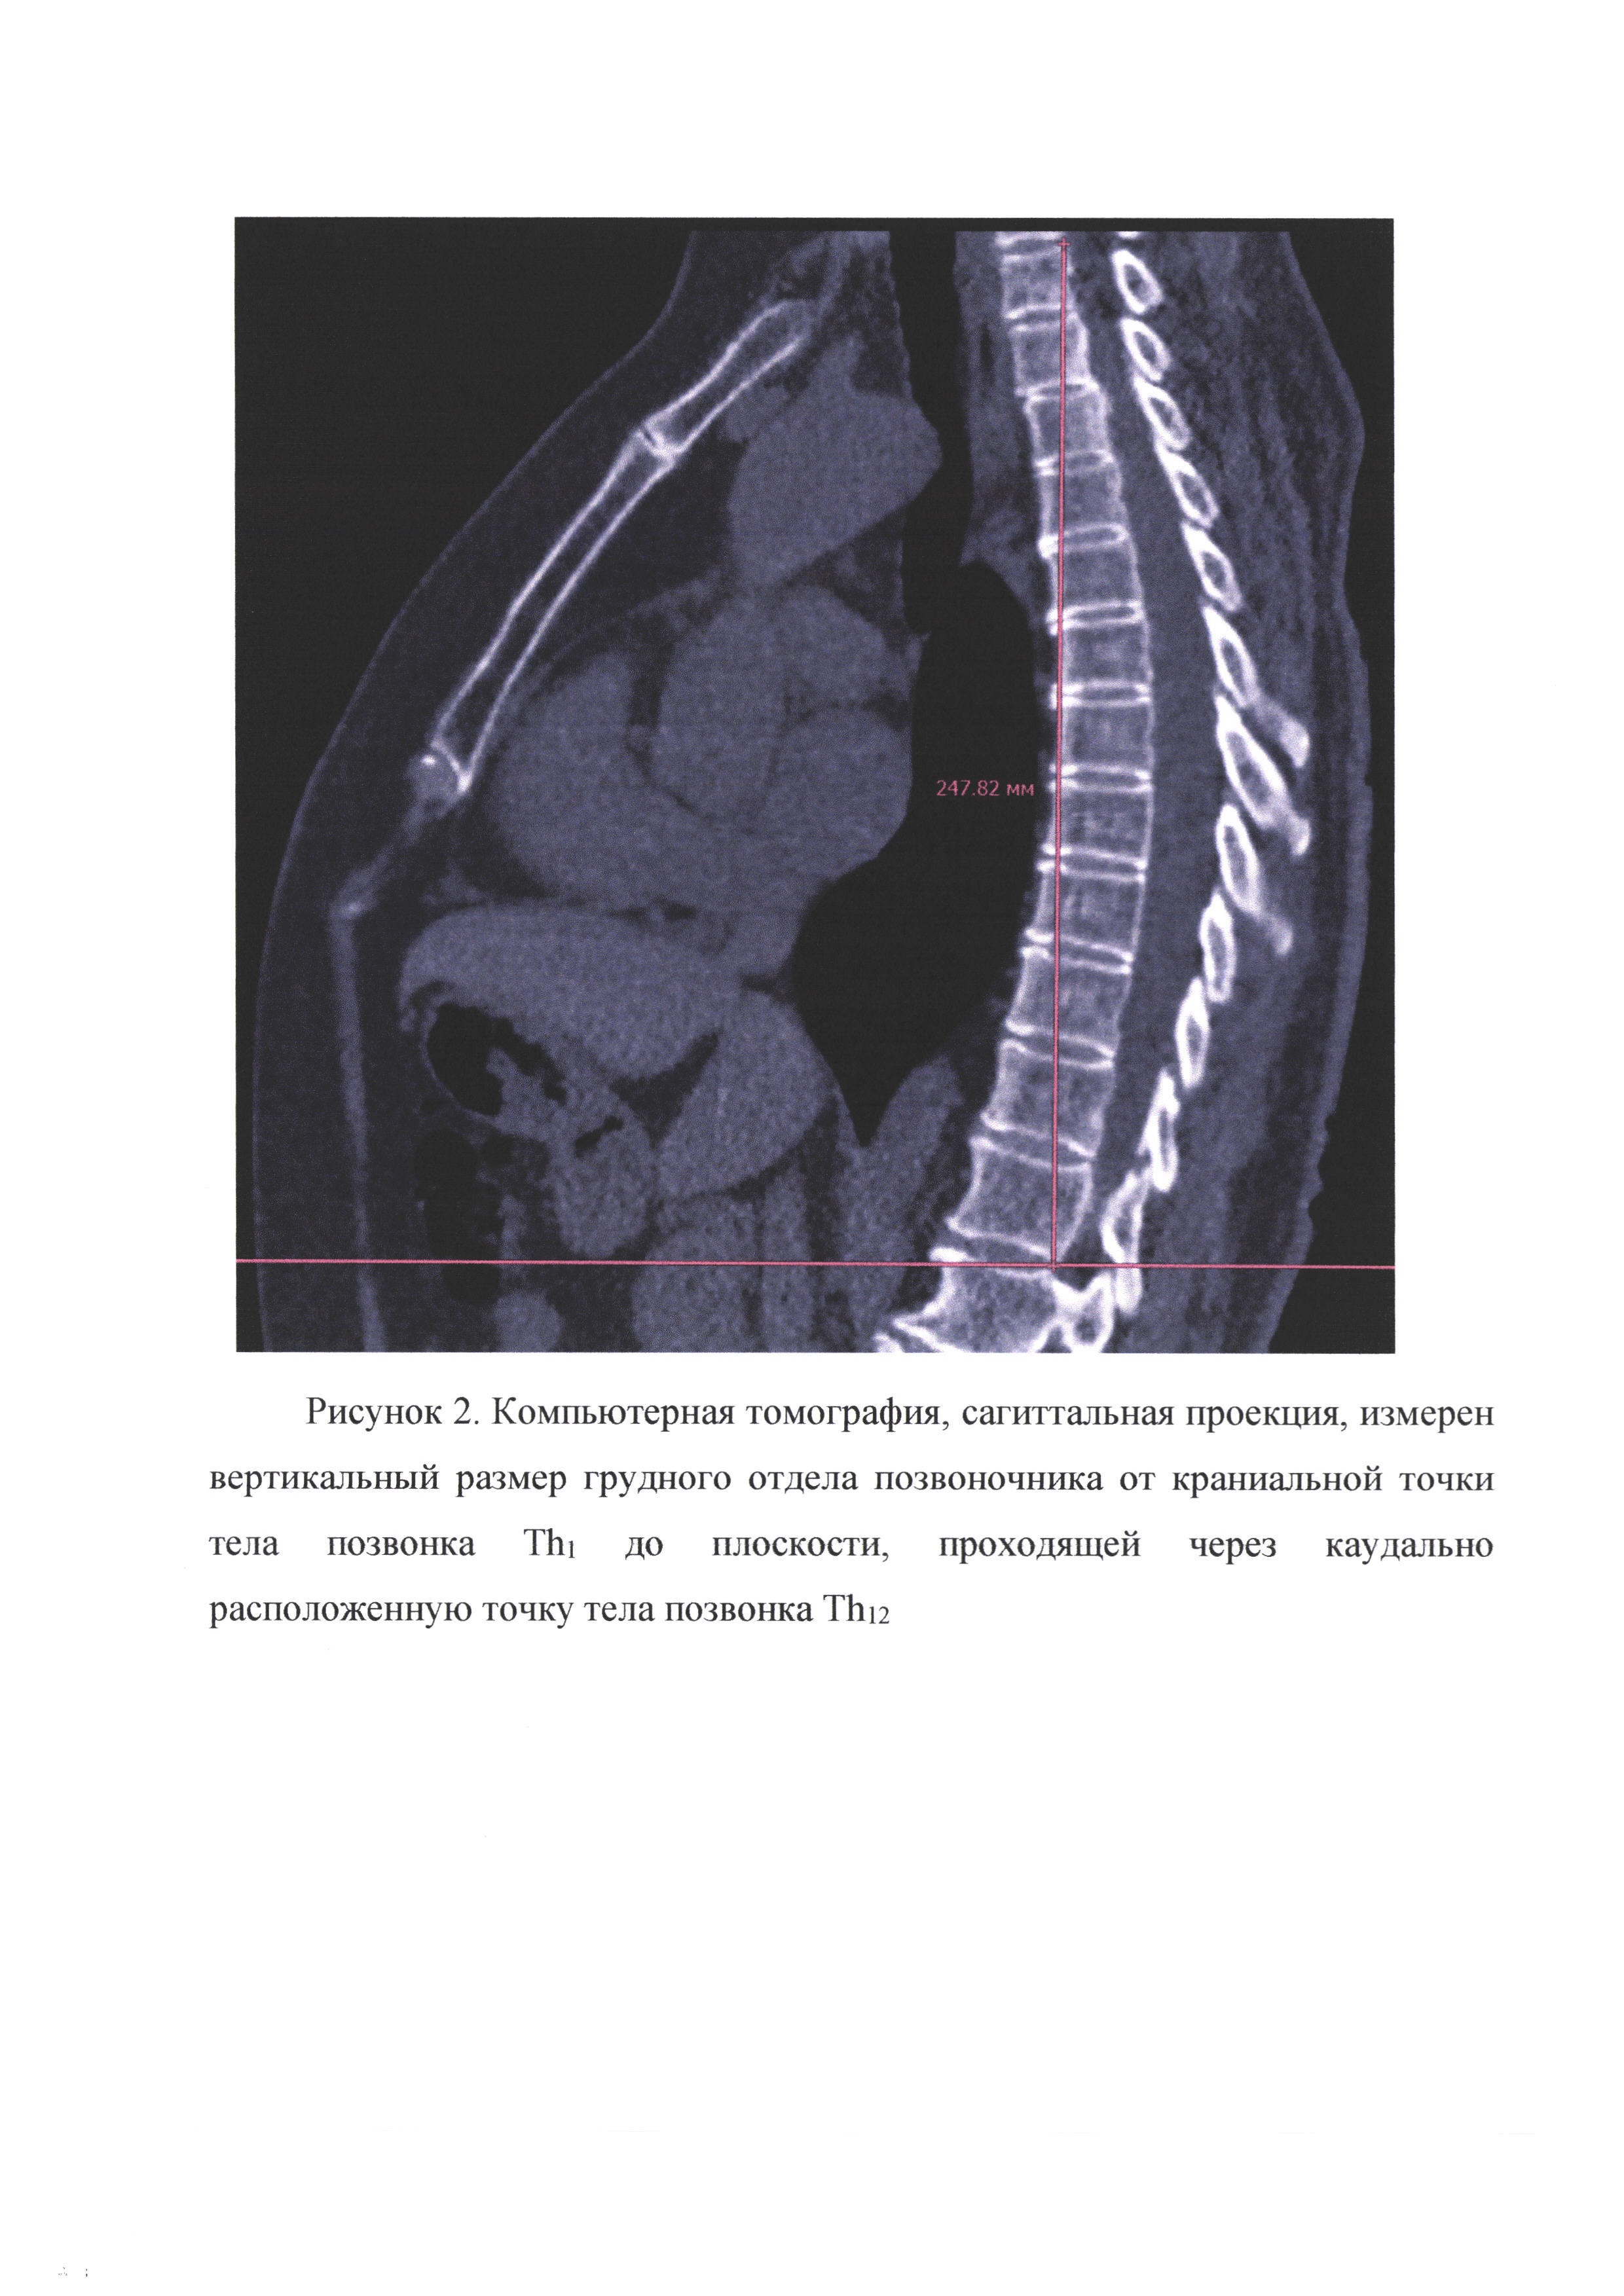

Предлагаемое изобретение относится к медицине, а именно к лучевой диагностике и позволяет определить индекс мышечной массы больного по данным компьютерной томографии при отсутствии информации о росте. Вычисленный таким способом индекс мышечной массы может быть использован для прогноза течения различных заболеваний, риска развития осложений и смертности. Индекс мышечной массы (ИММ) является суррогатным показателем, позволяющим оценить общую массу скелетных мышц человека, снижение которой является одним из критериев диагностики саркопении. Это заболевание представляет собой прогрессирующее и генерализованное заболевание мышечной ткани, которое ассоциировано с увеличением вероятности неблагоприятных событий, таких, как падения, переломы, малоподвижность и смертность. ИММ может определяться по общепринятой методике согласно европейскому консенсусу рабочей группы от 2018 г. (Cruz-Jentoft A.J., Bahat G., Bauer J. et al. Writing Group for the European Working Group on Sarcopenia in Older People 2 (EWGSOP2), and the Extended Group for EWGSOP2. Sarcopenia: revised European consensus on definition and diagnosis // Age Ageing. 2019. Vol. 48. №1. C. 16-31. https://doi.org/10.1093/ageing/afy169). Для этого необходимо по данным компьютерной томографии на аксиальном срезе на уровне позвонка L3 выделить площадь всех скелетных мышц (SMA - skeletal muscle area, см2), а также иметь данные о росте больного (Н, м). Ниже представлена формула для вычисления ИММ - SMIL3 (см2/м2): В литературе различными авторами представлена возможность достоверного определения ИММ и на других уровнях поясничного, а также грудного отдела позвоночника с использованием роста больного (Derstine ВА, Holcombe SA, Ross BE, Wang NC, Su GL, Wang SC. Skeletal muscle cutoff values for sarcopenia diagnosis using T10 to L5 measurements in a healthy US population. Sci Rep. 2018 Jul 27; 8(1):11369. doi: 10.103 8/s41598-018-29825-5.). Однако, если пациент находится в тяжелом состоянии или в целом отсутствует возможность нахождения в вертикальном положении для измерения роста (неврологические нарушения, заболевания опорно-двигательного аппарата), то определение ИММ по общепринятой методике не представляется возможным. В то же время определение этого показателя может потребоваться у таких больных как в клинической практике, так и при проведении научных исследований, так как он обладает важным прогностическим значением при различных заболеваниях (злокачественный онкологический процесс, хронические заболевания сердечно-сосудистой и респираторной системы, цирроз и др.), а также определяет риск развития послеоперационных осложнений. В частности, доказано, что саркопения является одним из факторов риска тяжелого течения COVID19 и повышенной смертности (Siahaan YMT, Hartoyo V, Hariyanto TI, Kurniawan A. Coronavirus disease 2019 (Covid-19) outcomes in patients with sarcopenia: A meta-analysis and meta-regression. Clin Nutr ESPEN. 2022; 48:158-166. doi:10.1016/j.clnesp.2022.01.016). Таким образом, общепринятая методика, использующая рост пациента, не позволяет определить ИММ при изучении прогностической роли саркопении у ряда больных в том числе с социально значимыми заболеваниями. В качестве аналога взята общепринятая методика определения ИММ на уровне позвонка L3 с использованием роста пациента (Cruz-Jentoft A.J., Bahat G., Bauer J. et al. Writing Group for the European Working Group on Sarcopenia in Older People 2 (EWGSOP2), and the Extended Group for EWGSOP2. Sarcopenia: revised European consensus on definition and diagnosis // Age Ageing. 2019. Vol. 48. №1. C. 16-31. https://doi.Org/10.1093/ageing/afy169) Недостатки: 1. необходимы данные KT на уровне позвонка L3 (при проведении КТ органов грудной клетки этот уровень не входит в область сканирования), 2. необходимы данные о росте больного. Ближайшие аналоги: 1. методика оценки мышечной массы на уровне позвонка Th12 только по площади мышц (Menozzi R, Valoriani F, Prampolini F, et al. Impact of sarcopenia in SARS-CoV-2 patients during two different epidemic waves. Clin Nutr ESPEN. 2022; 47:252-259. doi:10.1016/j.clnesp.2021.12.001; недостаток - отсутствие учета антропометрических параметров пациента не позволяет проводить статистически значимые исследования; 2. методика оценки мышечной массы на уровне позвонка Th12 с использованием роста больного (Nemec U, Heidinger В, Sokas С, Chu L, Eisenberg RL. Diagnosing Sarcopenia on Thoracic Computed Tomography: Quantitative Assessment of Skeletal Muscle Mass in Patients Undergoing Transcatheter Aortic Valve Replacement. Acad Radiol. 2017; 24(9):1154-1161. doi:10.1016/j.acra.2017.02.008; недостаток - необходимы данные о росте больного; 3. методика оценки мышечной массы на уровне позвонка Th12 с использованием длины грудного отдела позвоночника (Башков А.Н., Сушко А.И., Григорьева О.О., Шейх Ж.В., Удалов Ю.Д., Шикунов Д.А. Индекс мышечной массы на уровне позвонка Th12 как прогностический фактор летального исхода у пациентов с пневмонией, вызванной sars-cov2 // Медицинская радиология и радиационная безопасность. 2021. №. 1. С. 49-53. DOI: https://doi.org/10.12737/1024-6177-2021-66-1-49-53); недостатки - измерение длины грудного отдела позвоночника по данным КТ трудоемко, особенно у пациентов со сколиозом, в случае выраженного физиологического кифоза можно ожидать слабую корреляцию длины грудного отдела позвоночника и роста больного. Задачи: 1. Разработать способ определения ИММ на уровне позвонка Th12 по данным компьютерной томографии с использованием вместо роста пациента высоты грудного отдела позвоночника. Способ осуществляют следующим образом. Для решения поставленной задачи предложено определять площадь всех скелетных мышц (SMA - skeletal muss area, см2) на уровне середины тела позвонка Th12 на аксиальном срезе КТ исследования с помощью сегментации с использованием интервала плотности от -29HU до 150HU (рис. 1). Середина тела позвонка Th12 может быть точно установлена в сагиттальной плоскости. В этой же плоскости проводится измерение высоты грудного отдела позвоночника (HTh1-12, м) как кратчайшее расстояние между наиболее краниально расположенной точкой тела позвонка Th1 и плоскостью, проходящей перпендикулярно оси сканирования через наиболее каудально расположенную точку тела позвонка Th12 (рис. 2). В итоге индекс мышечной массы SMITh12 (см2/м2) вычисляется по формуле: Коэффициент 100 в формуле необходим для удобства оперирования данными, так как позволяет получать целые числа. По отношению к ближайшим аналогам заявляемый способ имеет следующие преимущества: - появляется возможность определения индекса мышечной массы на уровне позвонка Th12 при отсутствии данных о росте больного, когда он по различным медицинским причинам не может принять вертикальное положение; - появляется возможность определения индекса мышечной массы на уровне позвонка Th12 у пациентов, которым проводились как КТ органов грудной клетки, так и брюшной полости, так как уровень позвонка Th12 входит в область сканирования в обоих случаях; - определение индекса мышечной массы на уровне позвонка Th12 с использованием только данных КТ позволяет использовать предложенный метод как основу для создания программного обеспечения для определения ИММ с помощью «машинного зрения» на основе возможностей искусственного интеллекта. Заявляемый способ определения индекса мышечной массы апробирован клинически. В случайном порядке была набрана группа из 257 пациентов (120 мужчин и 137 женщин) в возрасте от 36 до 86 лет, которым было проведено КТ органов грудной клетки и брюшной полости. Каждому пациенту были определены ИММ на уровне позвонка Th12 с использованием высоты грудного отдела позвоночника согласно разработанной нами методике и роста. Также определялся ИММ по общепринятой методике на уровне позвонка L3 с использованием роста больного. В результате продемонстрирована очень высокая степень корреляции между ИММ на уровне позвонка Th12 с использованием высоты грудного отдела позвоночника (предложенная нами методика) и роста (r=0,947, р<0,001), что подтверждает возможность использования вместо роста пациента высоты грудного отдела позвоночника. Также высокая степень корреляции выявлена между ИММ на уровне позвонка Th12 с использованием высоты грудного отдела позвоночника (предложенная нами методика) и ИММ на уровне позвонка L3 (общепринятый аналог) (r=0,778, р<0,001). Разработанный способ в виду своей эффективности и относительной простоте исполнения может служить альтернативой методикам определения индекса мышечной массы с использованием роста пациентов, у которых невозможно измерить рост или при проведении научных исследований на основе большого количества данных КТ при отсутствии информации о росте больных.